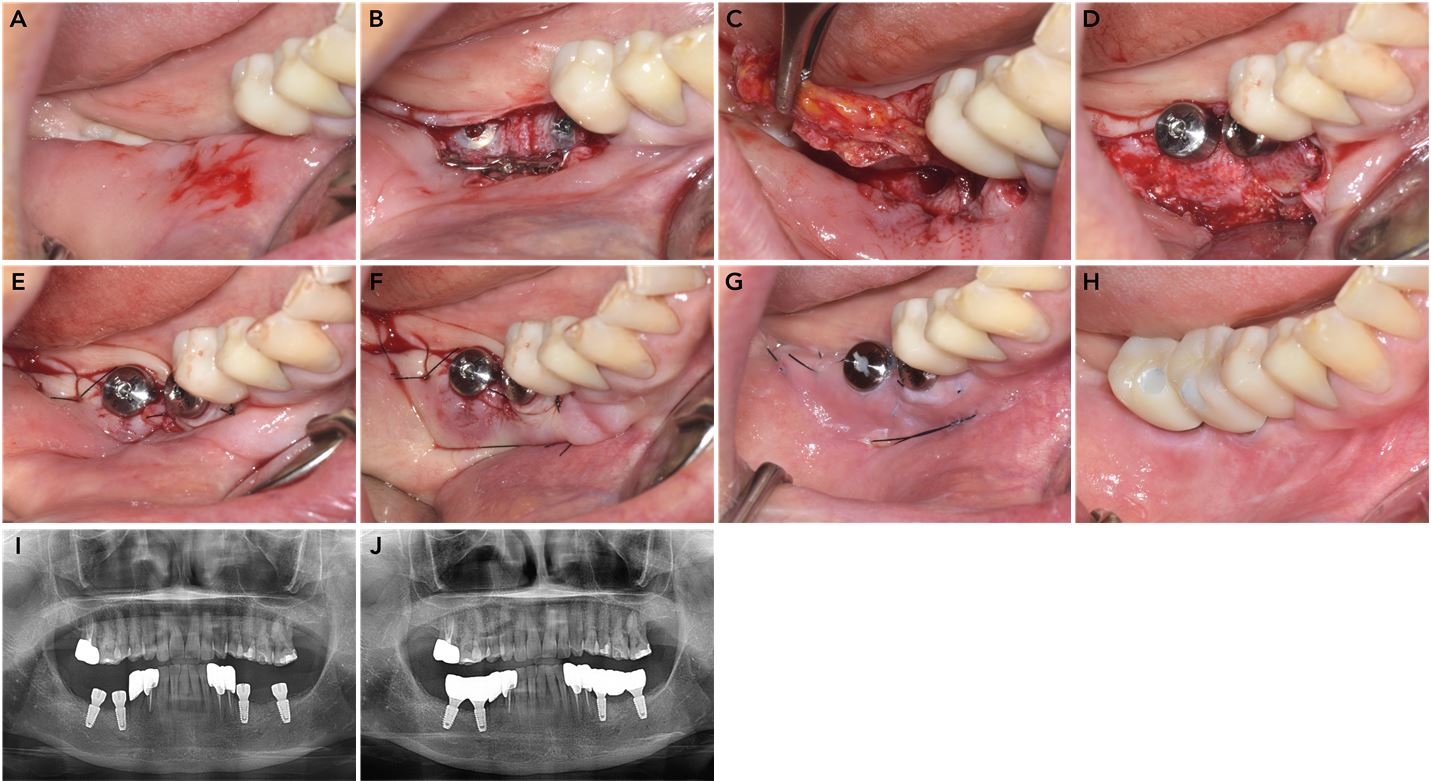

Implant second-stage surgery in the right mandible. (A) Preoperative occlusal view, (B) Elevation of full-thickness flap through a crestal incision with removal of the titanium meshes, (C) Removal of buccal connective tissue and periosteum during the thinning procedure, (D) Attachment of healing abutments, (E) Placement of simple interrupted sutures, (F) Placement of a double horizontal mattress suture to anchor the flap at the most apical part of the vestibule, (G) Suture removal after two weeks, (H) Final delivery of the implant-supported prosthesis, (I) Panoramic radiograph obtained after second-stage implant surgery, (J) Panoramic radiograph obtained after final prosthesis delivery.

The modified submucosal vestibuloplasty was performed during second-stage implant surgery after a four-month healing period (Figs. 4 and 5). Preoperative clinical photographs showed complete absence of both buccal and lingual vestibules, with a concave contour of the augmented alveolar ridge. Under local anesthesia, a midcrestal incision was made adjacent to the implant site, and a full-thickness flap was elevated to expose the titanium mesh. The titanium meshes and spacers were then removed. The apical portion of the flap was superficially elevated using a blade to achieve tissue thinning. The underlying connective tissue and periosteum were separated from the bone and apical tissues through a horizontal apical incision and blunt dissection. Healing abutments were attached, and simple interrupted sutures were placed around the healing abutments using 6‒0 monofilament nylon (Ethilon). A double horizontal mattress suture was used to anchor the flap at the most apical level of the vestibule using 5‒0 monofilament nylon (Ethilon). The newly formed vestibule remained stable following suture removal and after final prosthesis delivery.